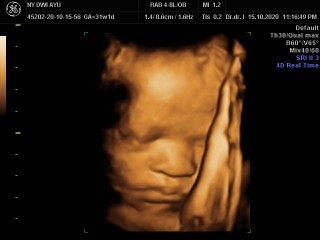

Waktu 34weeks baby boy, alhamdulilah sekarang udah masuk 36weeks

Ini waktu umu 31week . Smoga lahir sehat , normal . Aamiin